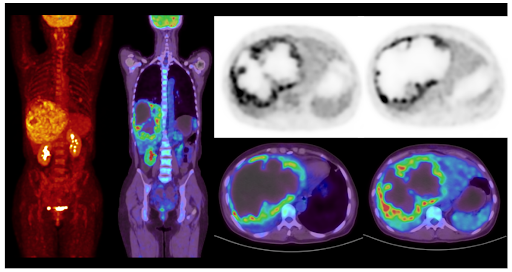

High Resolution Brain Imaging